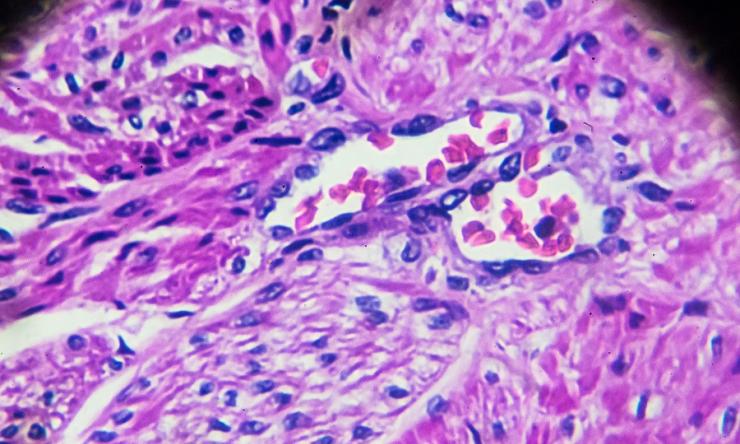

Adenocarcinoma of the endometrium: Cancer that develops in the glands lining the uterus, known as the endometrium; more than 95 percent of uterine cancers are endometrial cancer

Endometrial uterine cancers are sometimes preceded by pre-cancerous lesions called hyperplasia. Hyperplasia is an overdevelopment of the endometrial glands that can turn into cancer but is not cancer. It can range from “simple” (further away from cancer) to “complex” (closer to cancer) and with or without atypia, which is a precancerous change.

- Endometrial biopsy or D&C (dilation and curettage) - a procedure to remove tissue samples from the lining of the uterus for examination under a microscope. An endometrial biopsy is a quick procedure that is performed in the office. A D&C requires anesthesia and is performed in the operating room.